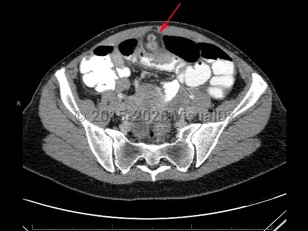

Meckel diverticulum

A Meckel diverticulum is a remnant of the omphalomesenteric duct in the distal ileum. Patients with a Meckel diverticulum typically present with painless hematochezia and/or bowel obstruction. Alternatively, a Meckel diverticulum should be considered if an abdominal mass is detected or in cases of abdominal pain, often right lower quadrant, of unclear etiology.

A Meckel diverticulum can predispose patients to intussusception, ulcer formation, bowel inflammation, perforation, or foreign body entrapment, all occurring at the diverticulum.